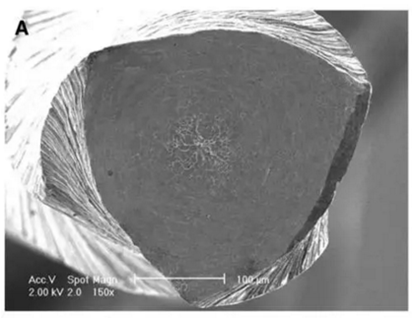

要深入了解器械斷裂的發(fā)生機(jī)制,就必須要在足夠的放大倍數(shù)下觀察斷裂面 (如上圖),也就是所謂的顯微斷口研究 (fractographic study)。這些為數(shù)不多的實驗大部分是針對機(jī)用鎳鈦銼。系統(tǒng)來說,斷裂機(jī)制主要分為剪切/扭矩破壞(shear/torsional failure)和疲勞破壞(fatigue failure) (Cheung et al. 2005)。

(a)疲勞破壞斷面特征示意圖;(b)SEM顯微斷面圖;(C)定常裂紋擴(kuò)展區(qū) (steady crack-growth region);(d) 疲勞條紋 (fatigue striations),箭頭提示裂紋產(chǎn)生瞬間的方向;(e)(f)器械的另外兩個切刃,無明顯裂紋產(chǎn)生,僅有微觀的韌窩出現(xiàn)

其微觀斷面特征主要有(Cheung & Darvell 2007):

1. 斷面一般有一個或多個裂紋源 (crack origin),然后每個都緊挨著定常裂紋擴(kuò)展區(qū) (steady crack-growth),之后就是快速裂紋擴(kuò)展區(qū) (rapid crack-growth area),里面都是一些形狀大小不規(guī)則的韌窩 (dimple)組織;

2. 疲勞條紋(fatigue striations)是特性表征,每個條紋代表的是當(dāng)材料受到載荷循環(huán)的壓應(yīng)力階段時,裂紋擴(kuò)展的方向。